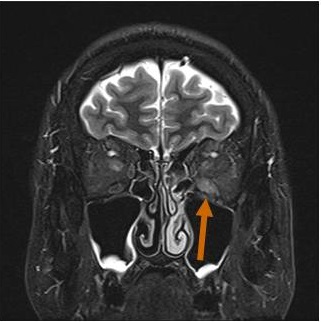

長崎甲状腺クリニック(大阪)では、メルカゾール(5mg)0.5T/日投与により数年間、甲状腺機能正常を維持している安定したバセドウ病患者にいきなり遅延型バセドウ病眼症が起こりました。そのMRI画像がこれです。

バセドウ病眼症(甲状腺眼症)診断目的のため行った眼窩MRI検査で、偶然、下垂体腺腫が見つかる場合があります。下は、左眼バセドウ病眼症(眼筋炎)、下垂体腺腫、上顎洞炎・鼻茸が合わせて見つかったケースです。下垂体腺腫が視神経交叉を押し上げているため、病態は複雑になります。